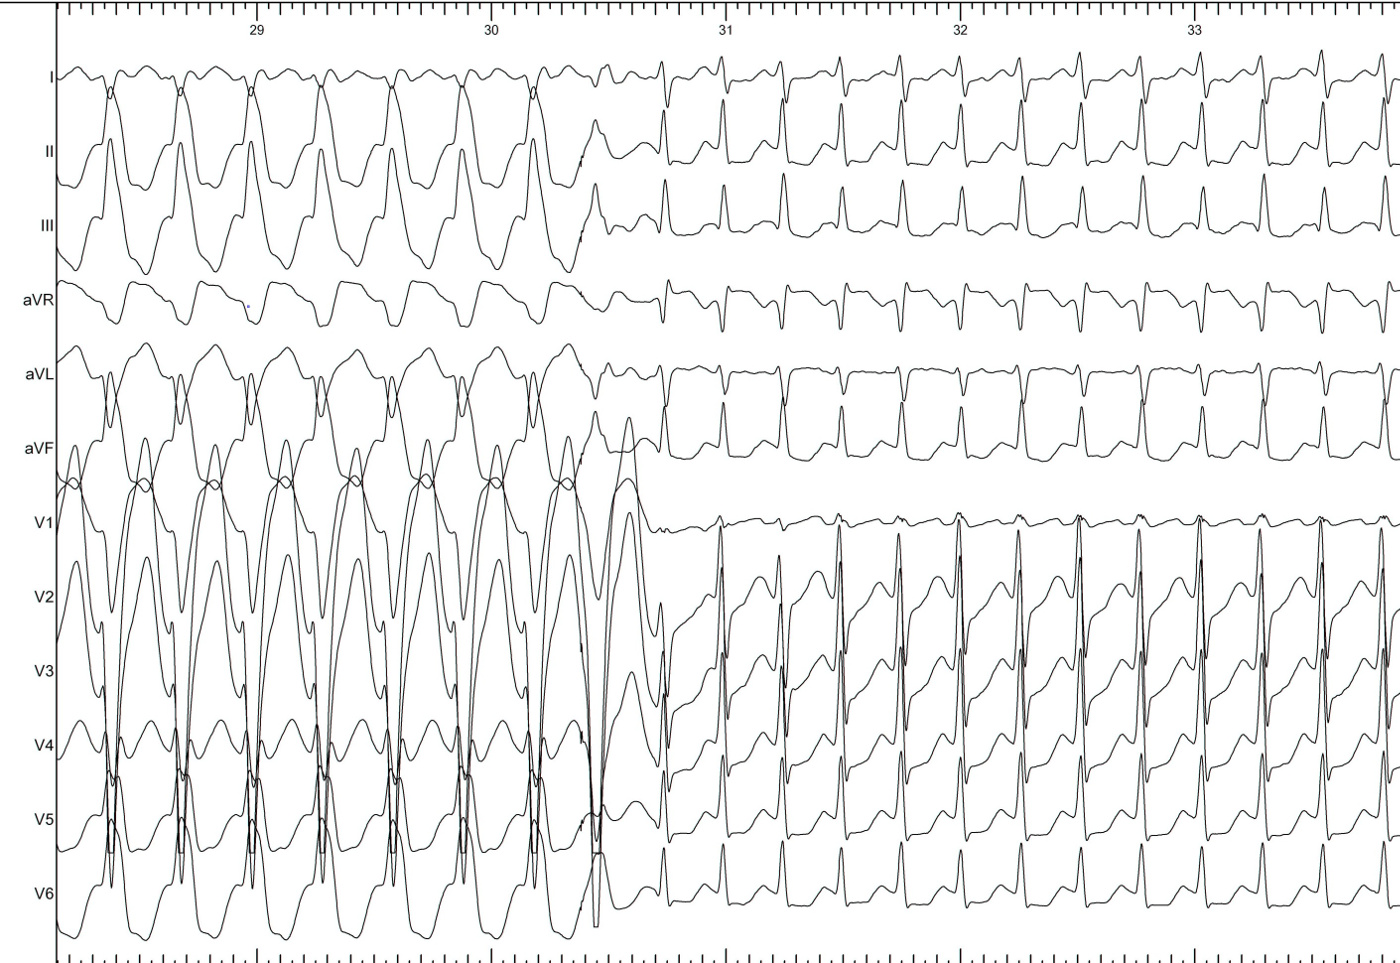

Bundle branch block

lbbb_narrow.jpg

lbbb_narrow_measurements.jpg

coumel.jpg